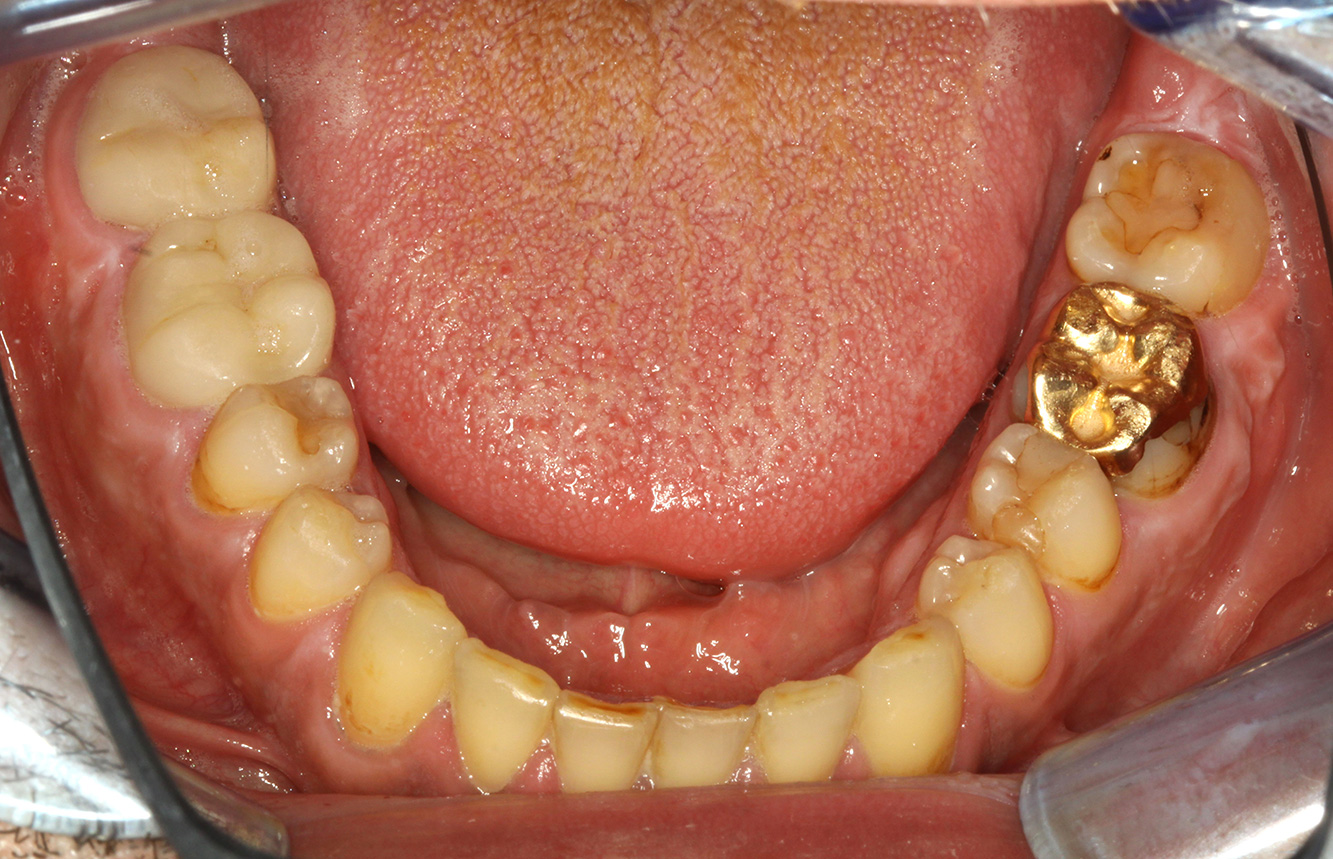

Durch den Herzklappenersatz und die Vorgeschichte einer Endokarditis lässt sich ein erhöhtes Komplikationsrisiko ableiten. Um das Risiko einer erneuten Entzündung zu mindern, ist eine Antibiotikaprophylaxe zu empfehlen (z. B. 2 g Amoxicillin 1h vor Sitzung). Trotz der bestehenden Dauermedikation mit einem Blutverdünner, ist in der Prophylaxesitzung nicht mit einem erhöhten Blutungsrisiko zu rechnen.

Für das Instruktions-/Motivationsgespräch sollte genügend Zeit eingeplant werden. Der negative Einfluss des Ernährungsverhaltens auf die Mundgesundheit (9) sollte dem Patienten anschaulich vermittelt werden. Auch im Hinblick auf die Endokarditis können die Zusammenhänge zwischen kariogenen Bakterien und kardiovaskulären Erkrankungen thematisiert werden (12). Wodurch die Motivation für eine nachhaltige Ernährungsumstellung gestärkt werden kann. Das Gespräch soll dem Patienten die Wichtigkeit einer guten häuslichen Mundhygiene vermitteln und ihn motivieren.